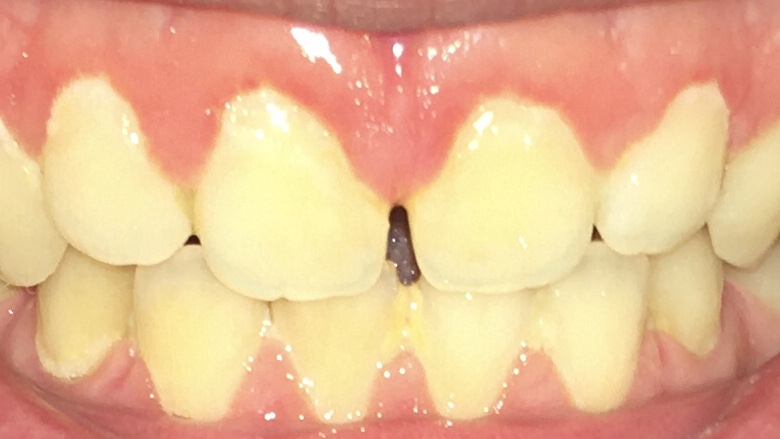

Сап медач.

Опустились дёсны в нескольких местах, обнажились шейки зубов. Чувствительные, болят от прикосновений, могут реагировать на холодное, горячее, сладкое.

Ситуация как примерно на пик2.